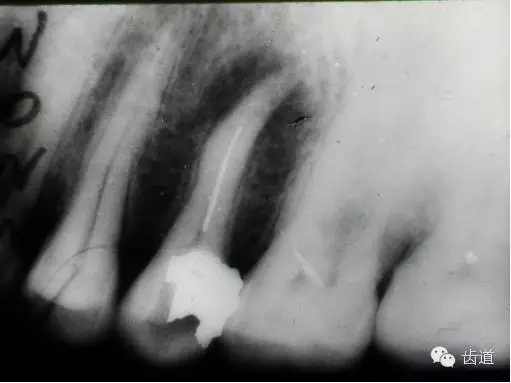

左下7根充后下唇麻木

左下5根管預(yù)備后下唇麻木